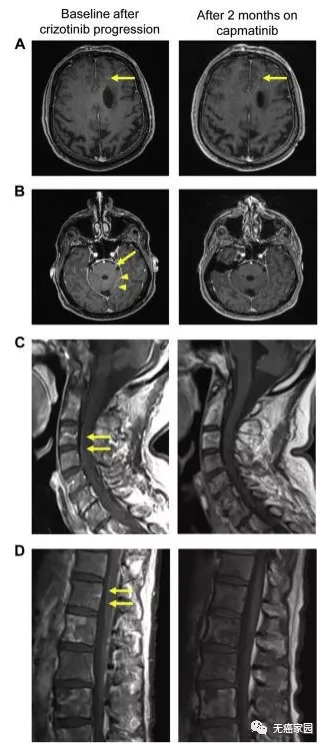

但不巧的是,病情急转直下,在治疗9个月后,患者开始出现脱水、低钙血症及精神错乱等问题,甚至还发生了脑实质和转脑膜转移,一直延伸到脊髓。在这万般危急时刻,医生经患者同意后,给其试用了卡马替尼,患者的病情迅速得到改善。

服用2个月的卡马替尼后,患者脑部左额叶的5 mm病变变成残留的的点状病变,病灶几乎快消失;左三叉神经和左小脑半球叶的软脑膜病变已检测不到病灶;治疗后软脑膜沿脊髓的增强信号也彻底消失。